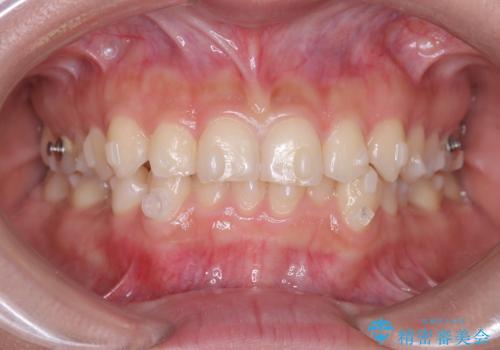

- 前歯のガタガタが気になるとのことでご相談いただきました。診察すると、歯列のスペースが不足し、前歯が重なっている状態でした。抜歯をせずに整えるため、歯と歯の間をわずかに削るIPR(歯列幅径削除)と、奥歯を後方へ動かす遠心移動を組み合わせてスペースを確保しながら並べる治療計画を立てました。

インビザラインを用いて歯を少しずつ移動させながら、IPRで微調整を行い、スペースを確保しました。また、奥歯を遠心移動させることで、前歯を自然な位置に並べることができました。治療後は、「ガタガタがなくなり、スムーズな歯並びになった」と患者様にもご満足いただきました。